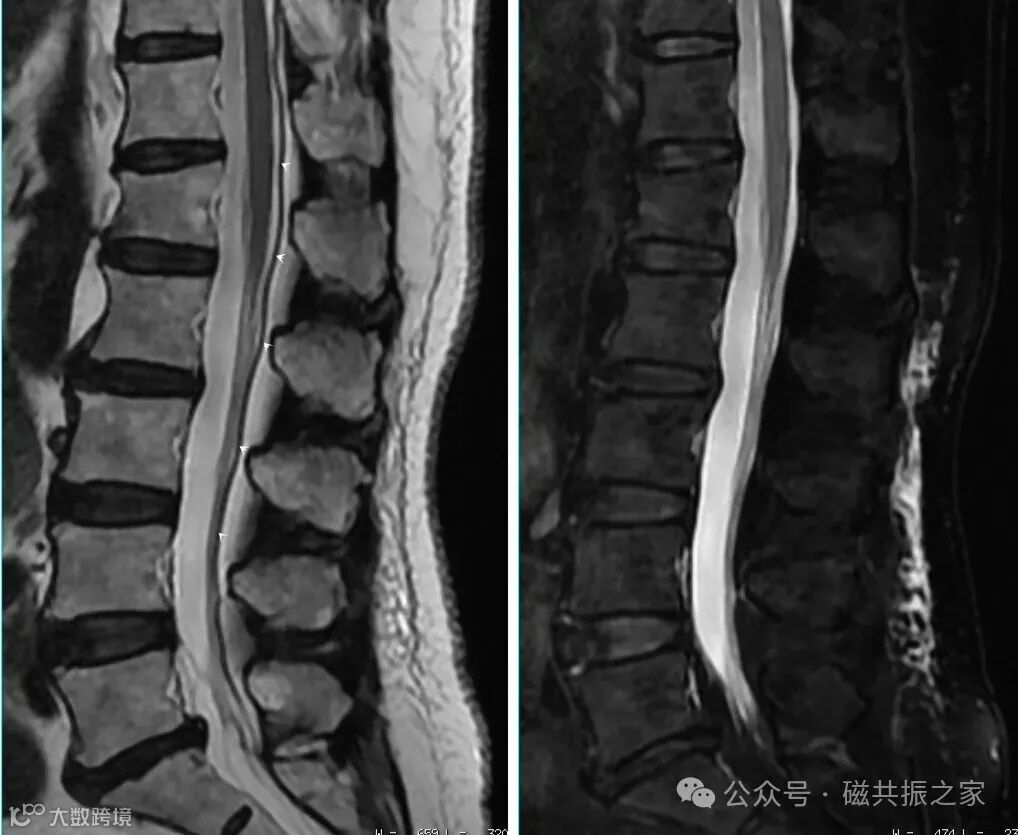

在对有金属植入物的扫描中,采用高带宽可有效改善其磁敏感伪影导致的变形失真,如高带宽+STIR的方式。

在非压脂或压脂不理想的图像上,由于水脂的频率差异易产生较为明显的化学伪影伪影。当这类伪影严重影响对图像的判读时,则建议使用高带宽来改善这类化学位移伪影。

这情况往往针对一些对扫描参数有极限需求的序列,如带宽与最小扫描FOV间的协同;获得更短的TE/TR值以及回波间隙等。这些极限值的使用不但可以缩短成像时间;减少质子失相位;减小错误相位积累;同时还可以达到改善相应伪影的目的。特别是对于那些需要实现最短TE,TR的序列,其带宽对其图像质量带来的影响巨大。